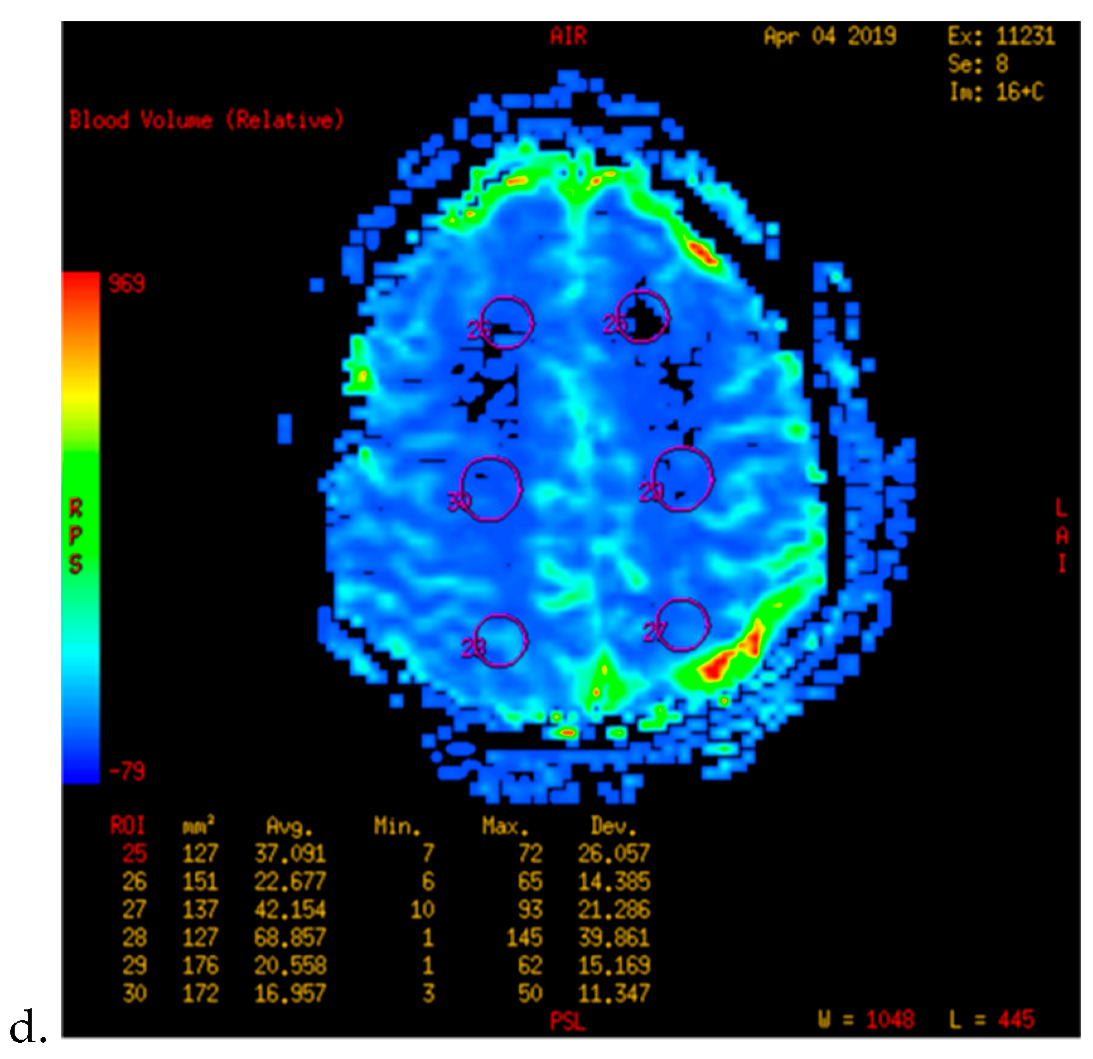

- Kameyama, M.; Fujimura, M.; Tashiro, R.; Sato, K.; Endo, H.; Niizuma, K.; Mugikura, S.; Tominaga, T. Significance of Quantitative Cerebral Blood Flow Measurement in the Acute Stage after Revascularization Surgery for Adult Moyamoya Disease: Implication for the Pathological Threshold of Local Cerebral Hyperperfusion. Cerebrovasc. Dis. 2019, 48, 217–225. [Google Scholar] [CrossRef]

- Tu, X.K.; Fujimura, M.; Rashad, S.; Mugikura, S.; Sakata, H.; Niizuma, K.; Tominaga, T. Uneven cerebral hemodynamic change as a cause of neurological deterioration in the acute stage after direct revascularization for moyamoya disease: Cerebral hyperperfusion and remote ischemia caused by the ‘watershed shift’. Neurosurg. Rev. 2017, 40, 507–512. [Google Scholar] [CrossRef]